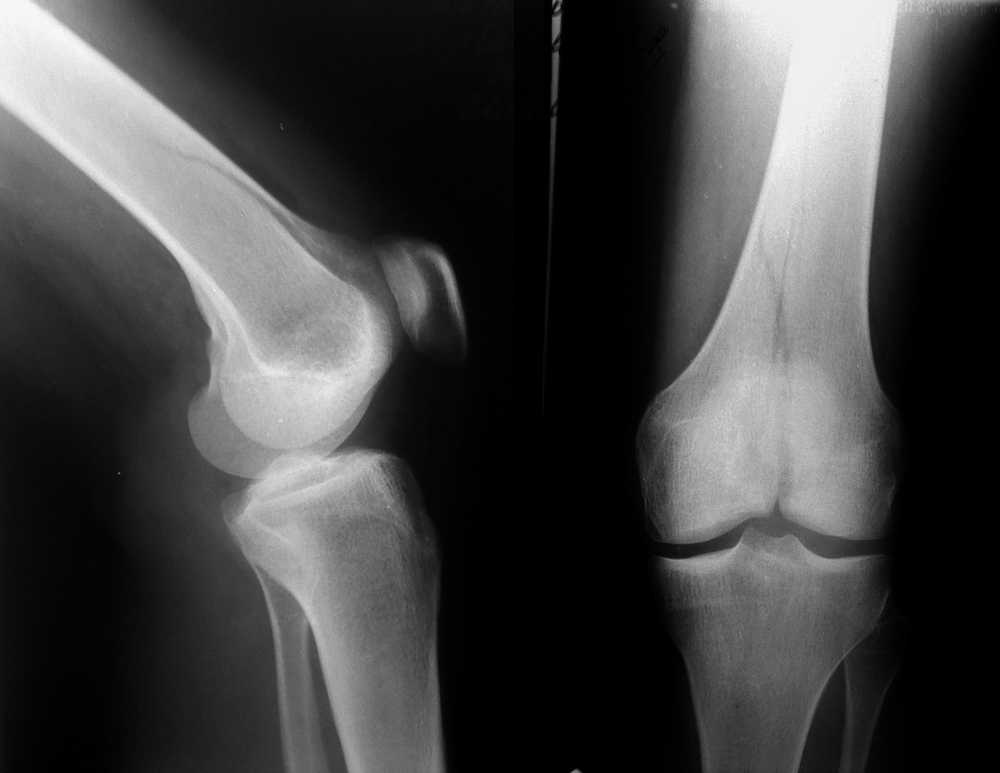

Перелом медиального мыщелка правой бедренной кости,по классификации Мюллера 33-В2.1

Женщина, 24 года, травма в быту, при падении с лестницы на согнутое колено. Кожные покровы в

хорошем состоянии, гемартроз умеренный, повреждения крестообразных связок пока не видно.

Вопрос стоит в следующем - достаточно-ли пары спонгиозных винтов и добавочной обычной

длинной тонкой Г-образной пластины (это все есть в больнице) или обязательно ставить

мыщелковую пластина для бедра, на всю длину перелома? P.S. Как обычно - вопрос в деньгах

пациента! ))))))